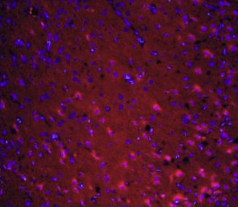

组织/细胞:大鼠脑组织;4%多聚甲醛固定石蜡包埋;

抗原回收:柠檬酸缓冲液(0.01M,pH 6),15min煮沸浴;37℃下封闭缓冲液(正常山羊血清)20分钟;

孵育:抗坏血性多克隆抗体,未结合1:200,4°C下过夜;二级抗体为山羊抗兔IgG,37°C下1:200稀释40分钟的Cy3结合。用DAPI(5ug/ml,蓝色)染色细胞核。